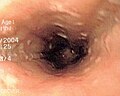

Category:Endoscopic images

This category contains images taken at the time of endoscopy of the GI tract, using esophagogastroduodenoscopy, colonoscopy, double-balloon enteroscopy, or ERCP.